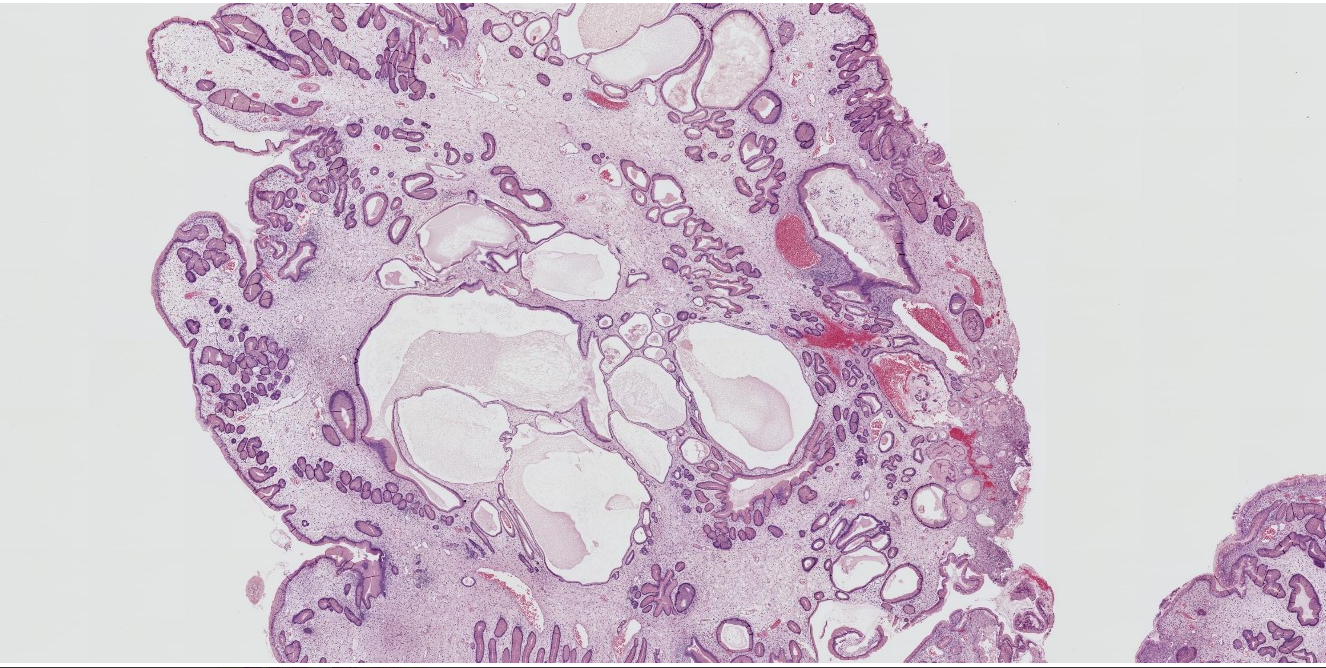

25M rectosigmoid polyp

Dx

Key features

Juvenile polyp

Key features:

Characterized by an abundance of edematous lamina propria with inflammatory cells and cystically dilated glands lined by cuboidal to columnar epithelium with reactive changes (gastric type epithelium??)

Dilated glands filled with mucus and inspissated inflammatory debris